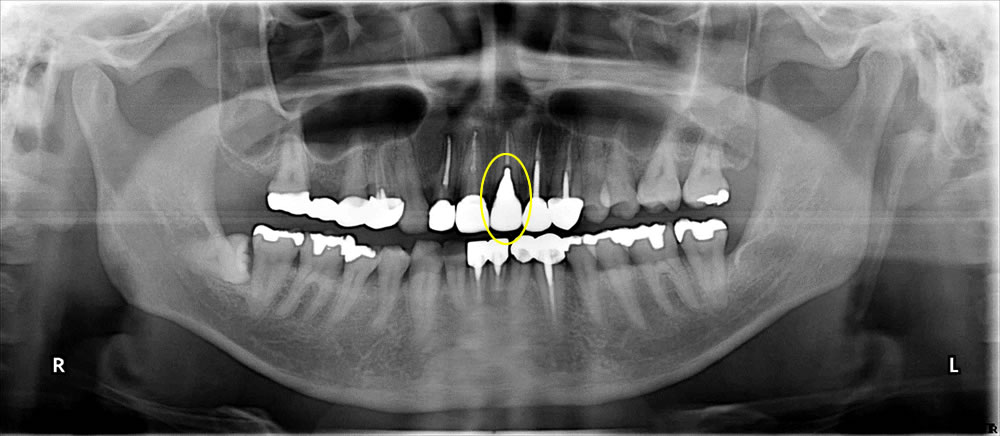

【レントゲン画像(術前)2016年9月10日】

こちらの患者さまは、左上顎の1番のかぶせ物が脱離し、本人がアロンアルファでかぶせ物を装着された状態で来院されました。口腔内所見では、自発痛や打診痛はありませんでしたが、患歯より排膿が認められました。歯周組織検査においては、4mm以上のポケットが93%、BOP(検査時の出血)は100%で、口腔内清掃状況は不良でした。咬合状態は臼歯部咬合関係が低く、ディープバイト(上顎の歯の咬み合わせが深い状態)でした。既往歴および全身所見に特記事項はありません。

口腔内の状態を把握し、適切なインプラント手術を実施するため、デンタルエックス線写真、パノラマエックス線写真、CT撮影、歯周病検査、唾液検査を実施しました。